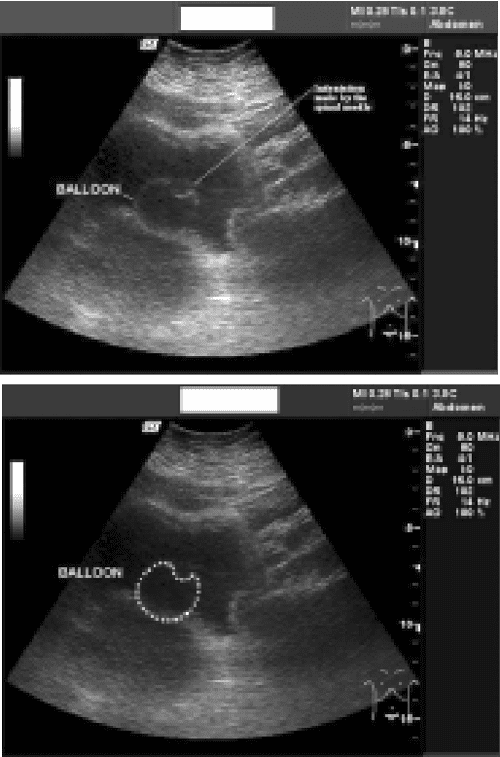

Balloon Catheter Ultrasound . This is indicative of an obstructed catheter, which can occur from a blood clot or other stricture. The sonographic image demonstrates the transverse view of the bladder distended with urine despite having a foley balloon in place (arrow). Balloon angioplasty, also known as percutaneous transluminal angioplasty (pta), is a minimally invasive procedure done to widen narrowed or obstructed blood vessels. The procedure accesses a blood vessel via a catheter inserted through an incision in the skin. Ultrasound can be used to watch inflation of the. An internal echo within the balloon due to the tubing as it runs through can usually also be seen on ultrasound. A patient’s anuria can be treated by simply flushing the catheter. Percutaneous transluminal balloon angioplasty represents the basic endovascular technique for the treatment of arterial or venous. Validation of imaging, analysis of.

Ultrasound for Foley Catheter Positioning & Obstruction Identification Balloon Catheter Ultrasound Validation of imaging, analysis of. A patient’s anuria can be treated by simply flushing the catheter. An internal echo within the balloon due to the tubing as it runs through can usually also be seen on ultrasound. The sonographic image demonstrates the transverse view of the bladder distended with urine despite having a foley balloon in place (arrow). The procedure. Balloon Catheter Ultrasound.